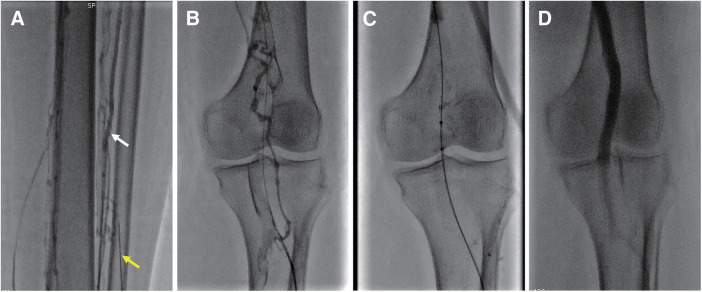

Purpose: The objective of this study was to evaluate the safety, efficacy, and feasibility of percutaneous mechanical thrombectomy (PMT) through a below-the-knee (BTK) approach for acute lower extremity deep venous thrombosis (DVT).

Methods: A retrospective review of DVT patients treated with PMT by the BTK approach at our center from April 2022 to August 2023 was performed. Their preoperative demographics, intraoperative data, and postoperative outpatient outcomes were analyzed.

Results: A total of 12 patients (67% men; mean age, 63 years) met the inclusion criteria. The BTK approach was successfully achieved in all patients through the posterior tibial vein (n = 1), anterior tibial vein (n = 2), and peroneal vein (n = 9). PMTs were achieved in 11 (92%) patients. Successful lysis (grade II and grade III lysis) was achieved in all patients with PMT. Four (33%) patients had residual venous occlusion over the popliteal vein. No intraoperative complications or bleeding events occurred in any of the patients.

Conclusion: PMT via BTK puncture seems to be a safe and effective approach for treating lower extremity DVT. It is reserved for highly select patients with a low risk of bleeding and is performed at centers that have experience with this procedure.